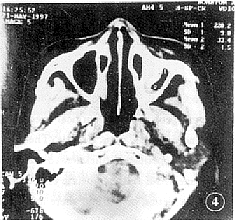

8例均行副鼻窦轴位平扫,层厚5 mm,层距5 mm。8例均显示受累副鼻窦粘膜肥厚,密度不均匀6例,均匀者2例;2例显示骨质虫蚀样破坏,1例骨质变薄,窦腔扩大,3例见软组织块影,CT值50~60 HU(图3);4例可见斑片状或条状高密度钙化影,CT值124~286 HU(图4);但未见侵及眶内或颅内扫描征象。

图4 条索状高密度致密影,CT值220 HU

影像学改变有一些具有诊断价值的表现[3,4]:站立或坐位平片显示受累副鼻窦粘膜增厚,均匀或不均匀窦腔密度增高但无气液平面,除非合并细菌感染;CT或平片示窦腔内软组织块影,因其为真菌性干酪样坏死组织而密度不均匀,边缘不清楚,部分显示与窦壁分离;因磷石灰,硫化钙或氧化锌等在坏死组织中沉积,或因出血而有含铁血黄素沉积呈条状或斑片状高密影,CT值在90~210 HU左右,亦有作者发现有金属样高密度影,CT值达1000 HU,具有特征性诊断价值[7];窦壁骨质破坏多呈虫蚀样或仅有骨质变薄,窦腔扩大,鲜有大块骨质破坏者,本组3例骨质破坏均由CT发现,平片未显示;如侵及眶内或颅内有相应的占位性改变。